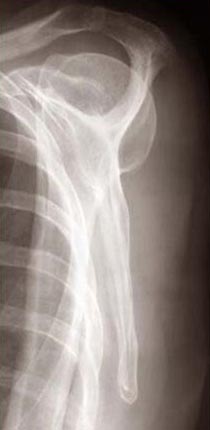

2003: As the body becomes fragile, what becomes of the self?

These images were shown in my MFA Thesis show at the Mass College of Art. In the first six images, I used the computer to combine my medical records with x-rays. The edges were created by encouraging the ink to run. The other four images are my x-rays that were modified in the computer and then printed large (2' x 4'). All images are inkjet prints on Vellum.